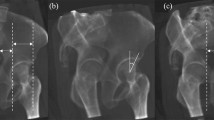

Lateral Center Edge Angle (LCEA) values were measured in a blinded fashion by a fellowship trained pediatric hip preservation surgeon pre-, intra-, and post-operatively (Fig. 2). LCEA has been determined to be a reliable measure of radiographic correction following PAO with high intra- and inter-observer reliability22,23. Intraoperatively, rotation and pelvic tilt were normalized to simulate a true AP pelvis (Figs. 3, 4). The intraoperative LCEA radiographic measures were compared to postoperative LCEA radiographic measures using the supine AP pelvis from the patient’s six-week postoperative follow-up visit.

Use of a novel imaging modality necessitates that the visualization of pelvic anatomy, performance of osteotomies, and acetabular reorientation is possible with the same quality as the previous standard of care. The benefit of reduction in intraoperative radiation exposure during PAO must be accompanied by similar image quality, and the ability to achieve similar results as compared to the SFII. In this case, the bias, or difference between the intraoperative and postoperative radiographs, was low in both groups without a significant difference in LCEA. Importantly, neither machine consistently over- nor under-estimated the intraoperative LCEA as compared to its respective patient’s postoperative LCEA. Additionally, on direct visual estimation, both the SFII and FPD produced similar quality images as observed by viewing the two images side by side (Fig. 6). Overall, these results indicate no significant difference between the image quality produced by the FPD fluoroscope as compared to the SFII.

Intraoperative fluoroscopic images compared to their anteroposterior (AP) pelvis radiograph taken 6-weeks postoperatively. (a) Patient 1 image taken by the Standard Fluoroscope with an Image Intensifier intraoperatively. (b) Patient 1 AP pelvis taken six-weeks postoperatively. (c) Patient 2 image taken intraoperatively by the novel Fluoroscope with Flat Panel Detector Fluoroscope. (d) Patient 2 AP pelvis taken six-weeks postoperatively.